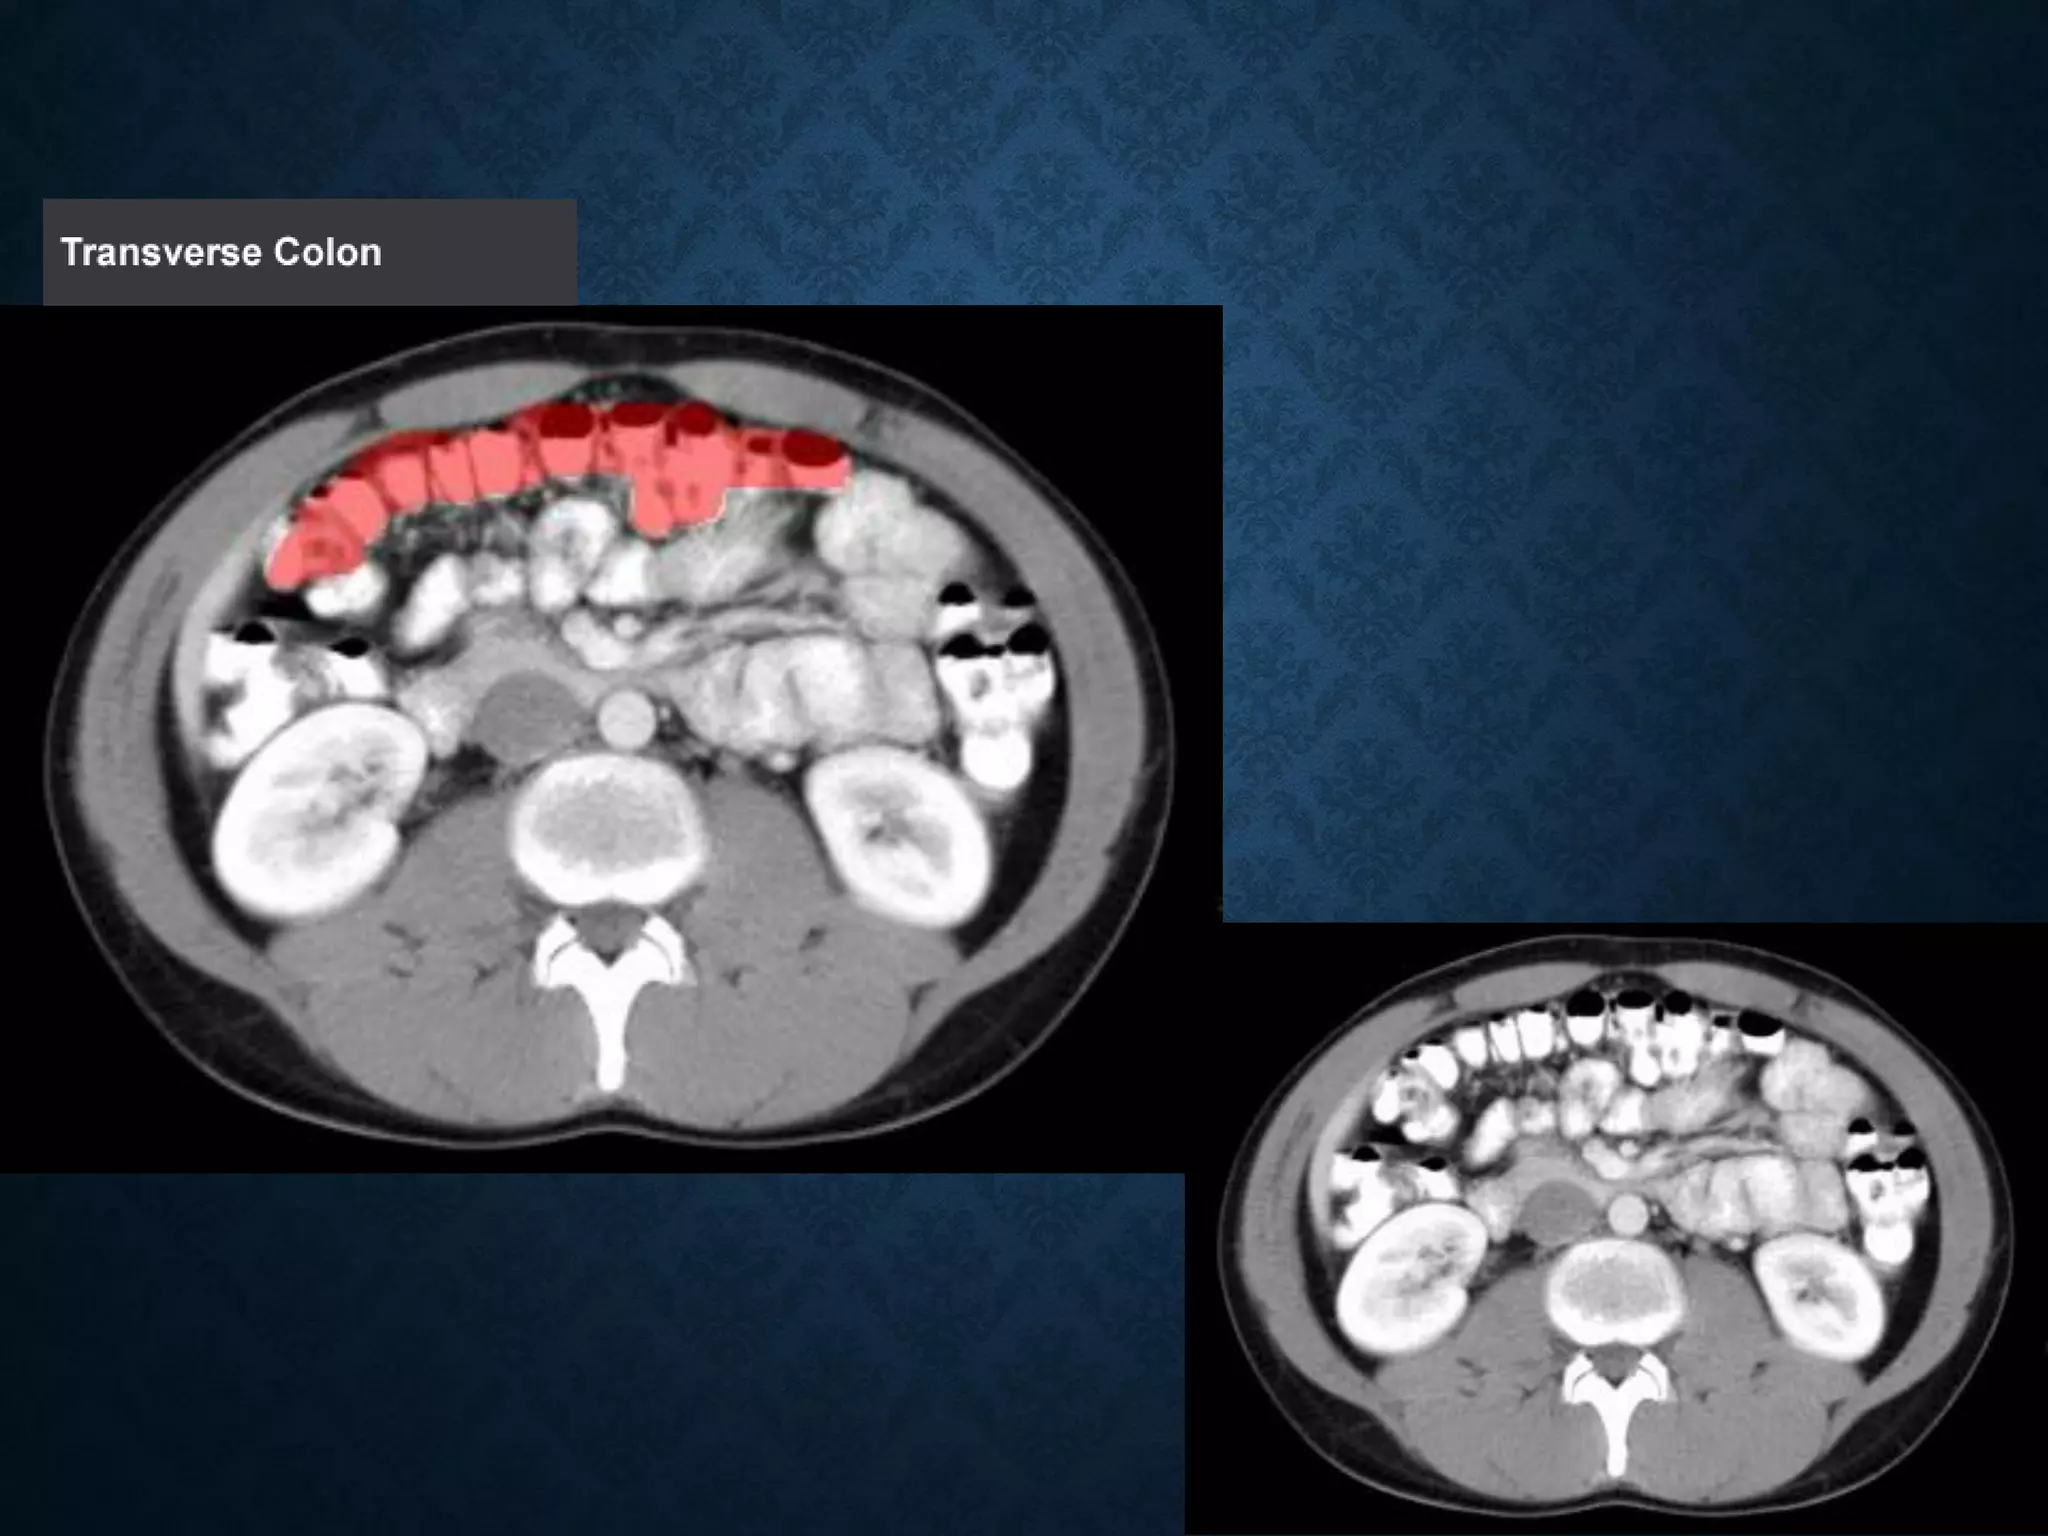

Identify the following structures in the body CT to the right. To view the location of the structure in the image click on

the label at the left and the structure will be indicated in the image. Abdominal CT scans typically begin just above

the diaphragm, so the first slice you see is of the lower chest.

Identify the followingstructures in the body CT to the right. To view the location of the structure in the image click on the label at the left and the structure will be indicated in the image. Abdominal CT scans typically begin just above the diaphragm, so the first slice you see is of the lower chest.